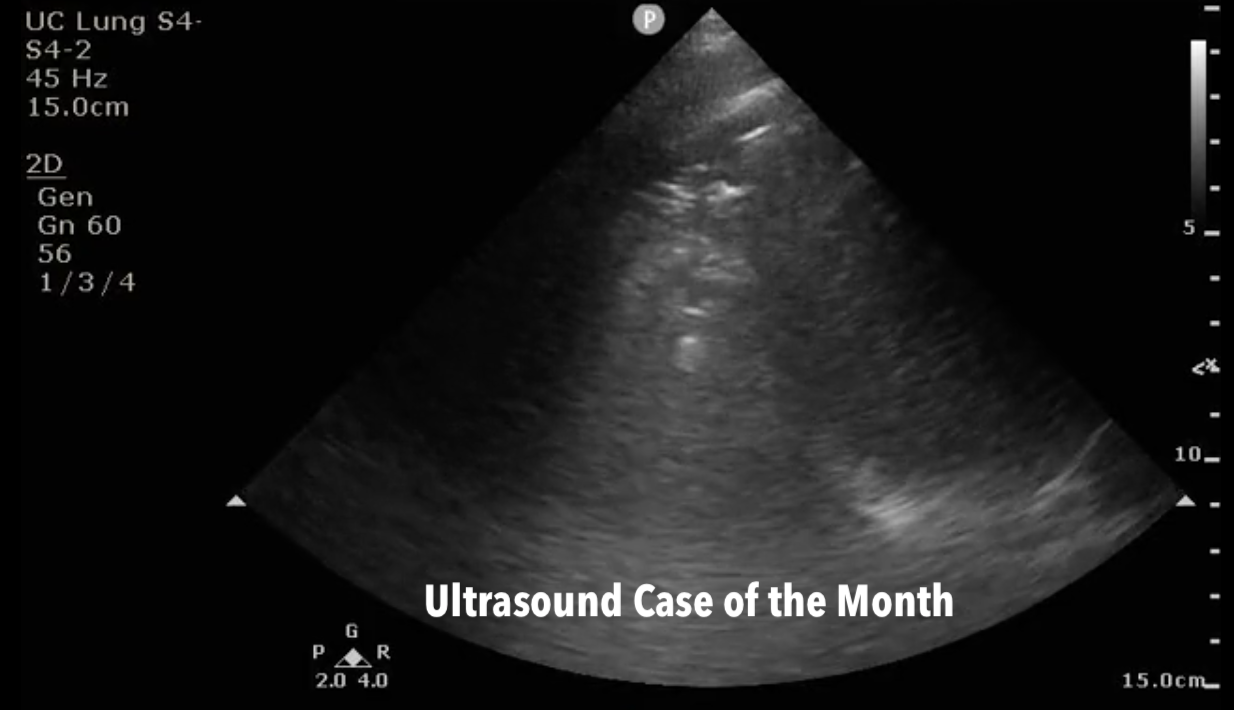

Ultrasound Case of the Month: To B-Line or not to B-Line - Sonographic Diagnosis of Pneumonia

/Historically, air was seen as the downfall of ultrasound, and thus assessment of the lungs was thought to be a fool’s errand. Recent experience suggests that ultrasound has a lot to offer our clinical assessment of pulmonary pathology. Dr. Broadstock takes us through a case of a hypoxemic tachypneic woman, with US serving as the star of the show.